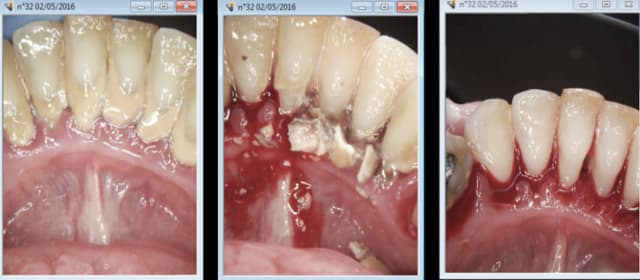

02/05/2016 à 21h55

Il faut s'adapter à notre nomenclature de merde sans pour autant en faire. -)

Endo, taille, empreinte, provisoire : 40 mn. Durée de RDV : 1H donc 20 mn pour se détendre et ré attaquer de plus belle le patient suivant. -) -)

J'ai merdé quelque part : devinez ou ? -)

Sinon: qu'est-ce que c'est que cette béchamel autour des dents? De la plaque?

> Sinon: qu'est-ce que c'est que cette béchamel autour des dents? De la plaque?

J hésiterais entre un double cheese et de la crêpe bretonne :-)

30 mn de plus pour RTE taille de la 5. Pfffff taux horaire de merde ! -)))

Pour la plaque ? mais ca c'est que dalle ! je ne m'en suis meme pas aperçu ! -)))

Sinon enlaye j'essaie de faire un effort pour les limites de préparation. -))